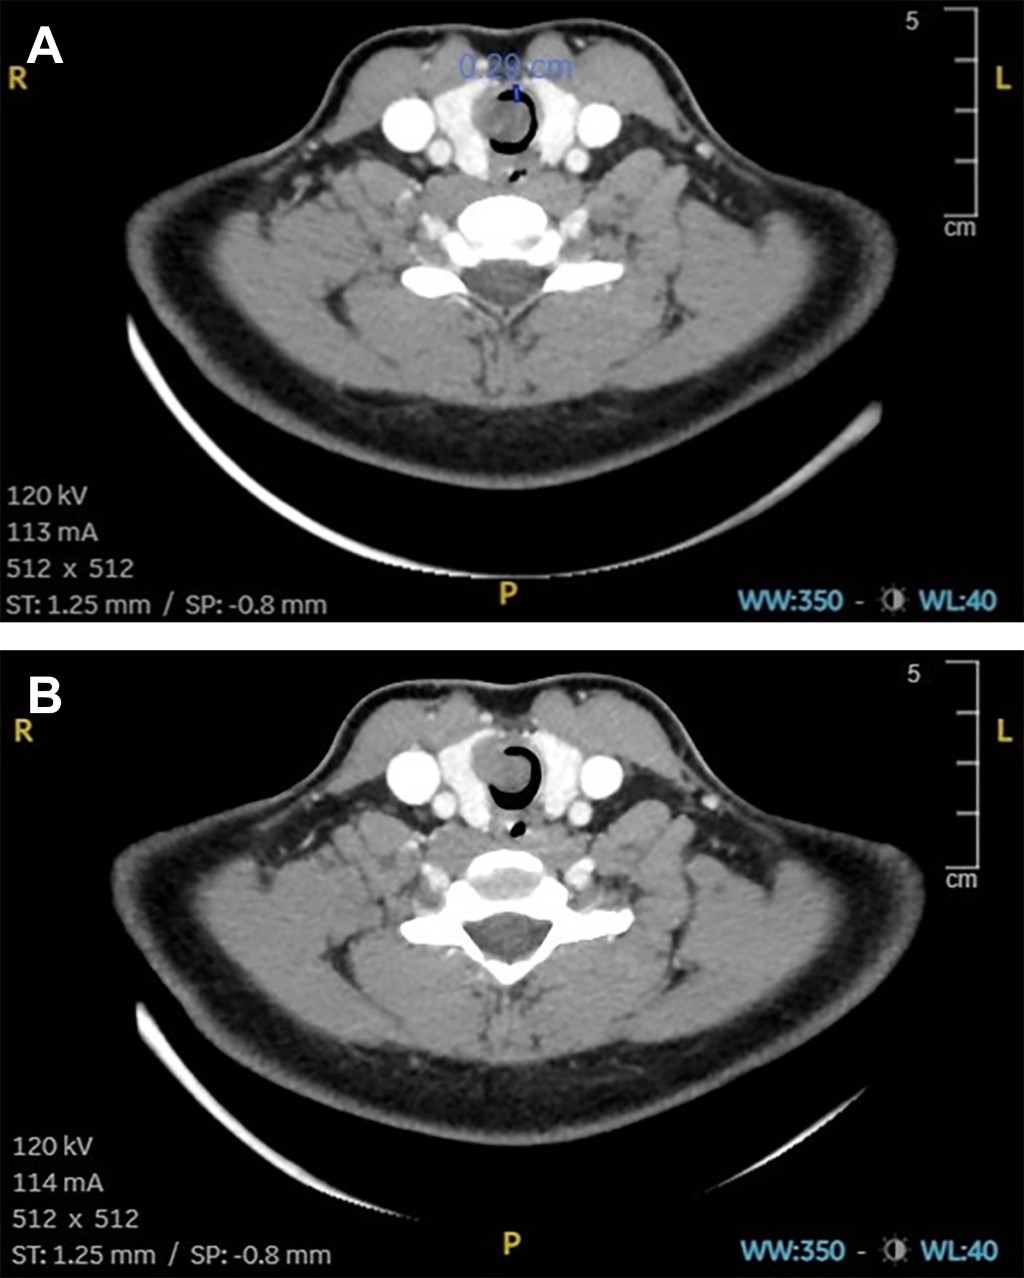

A 47-year-old male patient, with no significant medical history, aside from smoking 10 cigarettes daily, was found by prehospital emergency medical services on the stairs of his apartment after an unwitnessed fall. He exhibited signs of traumatic brain injury with an open wound on his forehead and obtundation, with a Glasgow Coma Scale score of 7 on collection. To secure the airway, rapid sequence induction orotracheal intubation was performed due to the patient's unknown fasting status. Two attempts were made using endotracheal tubes of different sizes (7.5 mm internal diameter and 6.5 mm internal diameter) without success, even despite a Cormack-Lehane grade IIa view. Despite multiple maneuvers and adjustments, the tubes could not advance beyond the glottis due to narrowing of the airway secondary to previously unrecognized tracheal stenosis due to a tracheal tumor (Figure 1).

Figure 1